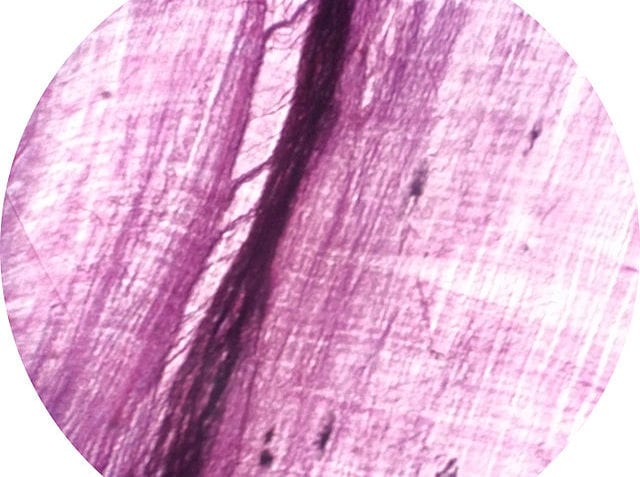

Músculo esquelético: también conocido como músculo voluntario o estriado, es un tejido compuesto por largas células multinucleadas y cilíndricas que cuentan con un gran número de mitocondrias. Esta clase de tejido puede encontrarse en el 90% de todos los músculos del cuerpo humano, unido al esqueleto dentro de aponeurosis y cartílagos. Por lo general, estos se contraen de forma voluntaria, aunque pueden hacerlo de forma involuntaria como resultado de enfermedades. Estos se encargan de mover y desplazar el cuerpo, de proteger al organismo, de mantener la postura y de generar calor, entre otras funciones. Usualmente se clasifican en fusiformes, unipeniformes, bipenniformes, multipenniformes, anchos, planos, cortos, bíceps, digástricos y poligástricos.